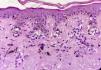

El problema de las lesiones pigmentadas planas de la cara desde el punto de vista del patólogoLos patólogos que se enfrentan a una lesión melanocítica proveniente de una biopsia de una lesión pigmentada plana de la cara de una persona mayor deben tener en mente que los criterios de diagnóstico para melanoma en este caso son diferentes a los clásicos utilizados para la disquisición entre nevo y melanoma en otras topografías. Por ejemplo, en una biopsia proveniente de una lesión como la de la figura 1 la sola presencia de nidos en la unión dermo-epidérmica, y abundante elastosis solar, ya debe hacernos pensar en melanoma in situ (fig. 3). No importa si los melanocitos son atípicos, o si ascienden en forma pagetoide o si comprometen el folículo; el diagnóstico es más probablemente melanoma. ¿Por qué? Porque la lesión de la figura 1 nunca puede ser un nevo de la unión ni un nevo displásico ni ningún tipo de nevo melanocítico.

En suma, la presencia de nidos de melanocitos en la unión dermo-epidérmica con cúmulos de elastosis solar en biopsias de la cara es altamente sugestiva de melanoma. En ocasiones es obligado realizar técnicas de inmunohistoquímica para el diagnóstico de lentigo maligno, sobre todo en los que se presentan en forma exclusivamente lentiginosa, así como frente al diagnóstico diferencial con queratosis actínicas pigmentadas, queratosis liquenoides o hiperplasia de melanocitos en piel fotodañada.